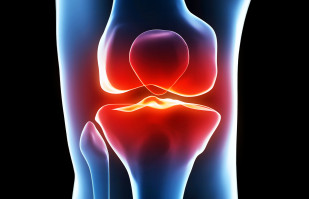

Joint Replacement

Rothman Orthopaedics' Joint Replacement Program is one of the nation's top joint replacement centers, performing more than 17,000 joint surgeries annually.

If you experience pain in any of your joints due to physical activities such as walking, running, and climbing stairs, it may be time to have a Rothman Orthopaedic Institute specialists diagnose your case. Joint replacement may be the answer for you. When simply sitting in a favorite chair or sleeping in your bed causes enough pain to wake you or make your life extremely uncomfortable, joint replacement may be able to get you back to an active lifestyle with less pain.